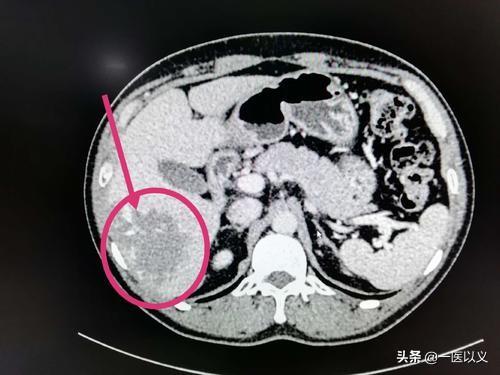

Bei der obigen Aufnahme handelt es sich um ein CT-Bild eines Leberhämangioms mit einem Schatten geringer Dichte im rechten Leberlappen mit klaren Rändern und progressiver Anreicherung vom Rand zur Mitte nach der Anreicherung.